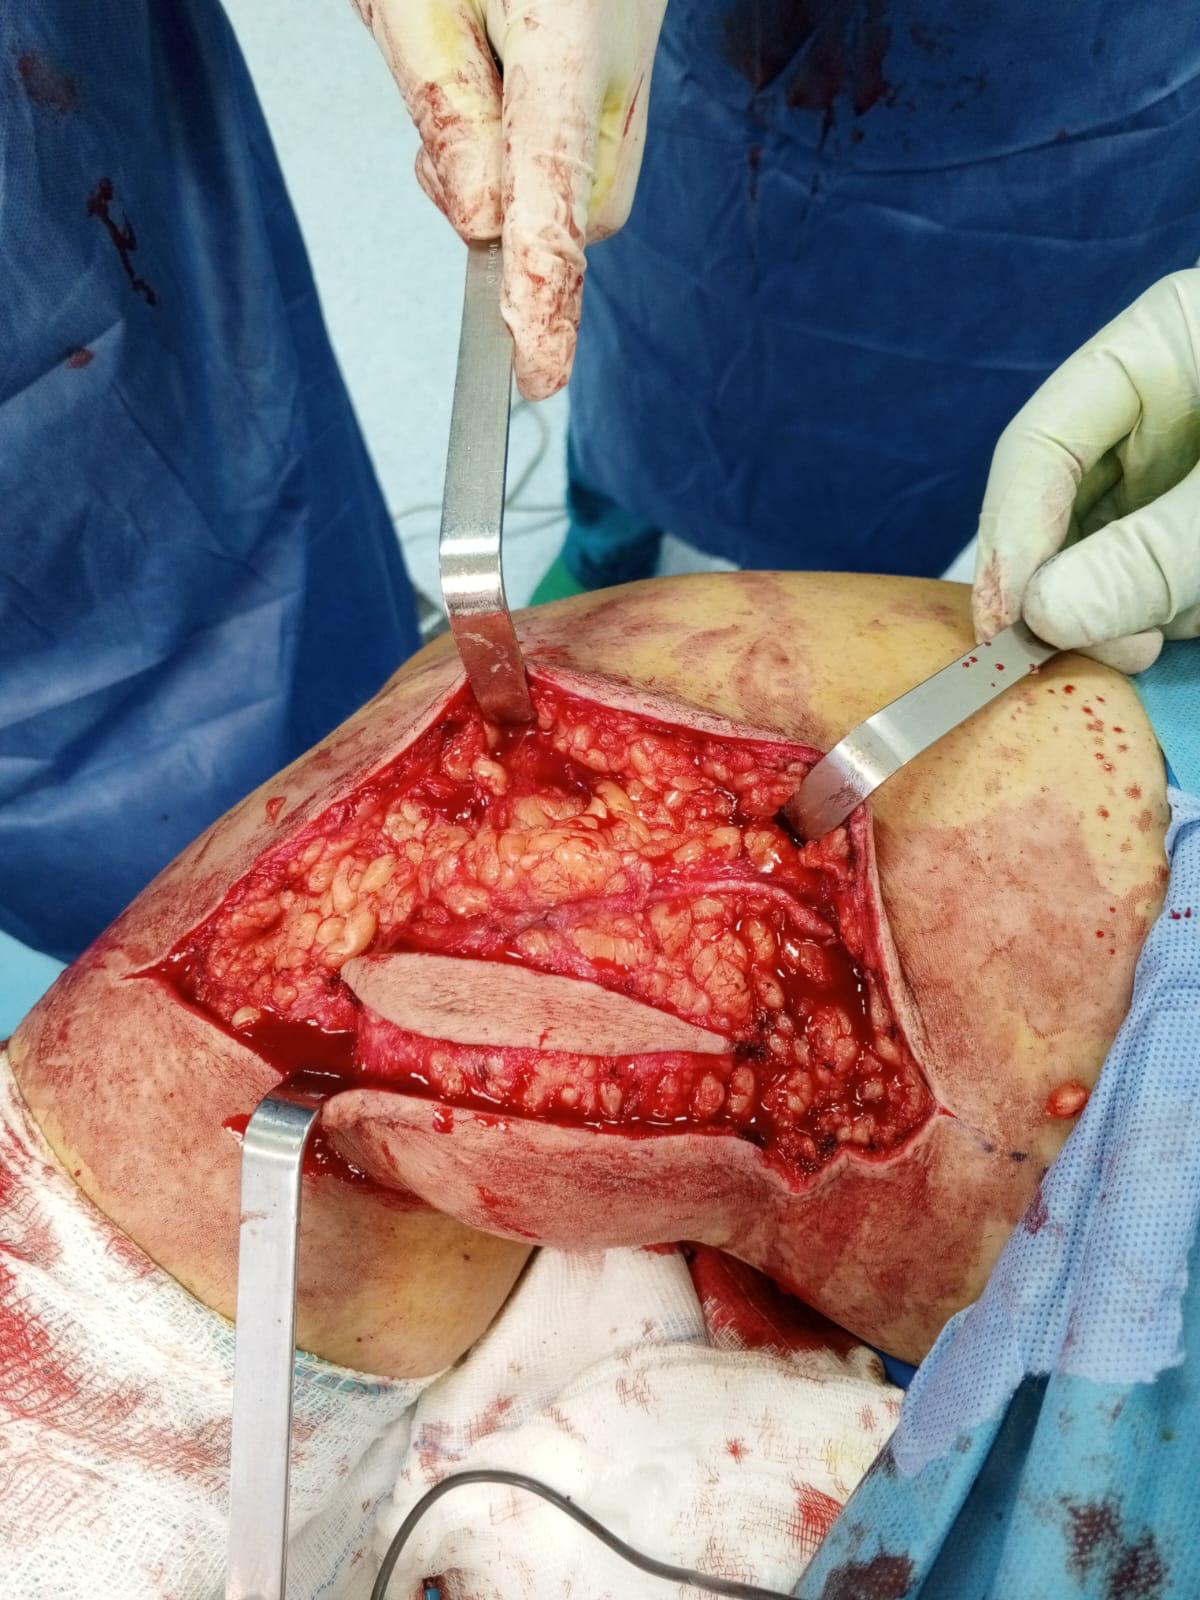

Muscle Cancer